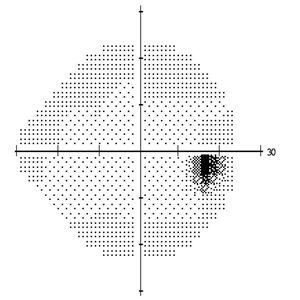

视物变形视野中心黑影遮挡,你的黄斑岌岌可危

因为黄斑位于视网膜的中心位置,当累及到黄斑区时,还可能导致黄斑前膜、黄斑裂孔及黄斑劈裂等严重病变。由于黄斑掌控是中央视力的重要区域,一旦出现病变,有可能严重影响视功能。

当黄斑出现上述病变后,随着疾病的进展,视力将明显减退,眼前中央黑影,视物变形,比如观察门框或窗户等直线物体时线条扭曲、甚至部分缺失,伴有色觉减退等症状,如果不积极治疗,患者后很可能失明。

(黄斑病变患者的视野)